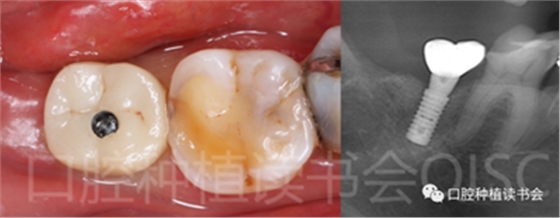

5.4.3 術(shù)后第10周,47戴入最終種植冠,X片確認(rèn)基臺(tái)就位準(zhǔn)確(圖25),以30N.cm扭矩旋緊基臺(tái)螺絲(圖26)。

5.4.4 種植冠封閉螺絲孔后,調(diào)合,拋光,完成最終修復(fù)(圖27);戴牙前CBCT顯示:種植體頰側(cè)骨板厚度為2.88mm;47種植冠獲得了良好的穿齦輪廓,并維持了正常的頰側(cè)牙弓輪廓。